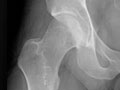

Extremity X-Ray

An extremity X-ray is a picture of your hand, wrist, arm, foot, ankle, knee, hip, or leg. It is done to see whether a bone has been fractured or a joint dislocated. It is also used to check for an injury or damage from conditions such as an infection, arthritis, bone growths (tumours), or other bone diseases, such as osteoporosis.